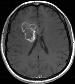

Machine learning has been widely adopted for medical image analysis in recent years given its promising performance in image segmentation and classification tasks. The success of machine learning, in particular supervised learning, depends on the availability of manually annotated datasets. For medical imaging applications, such annotated datasets are not easy to acquire, it takes a substantial amount of time and resource to curate an annotated medical image set. In this paper, we propose an efficient annotation framework for brain MR images that can suggest informative sample images for human experts to annotate. We evaluate the framework on two different brain image analysis tasks, namely brain tumour segmentation and whole brain segmentation. Experiments show that for brain tumour segmentation task on the BraTS 2019 dataset, training a segmentation model with only 7% suggestively annotated image samples can achieve a performance comparable to that of training on the full dataset. For whole brain segmentation on the MALC dataset, training with 42% suggestively annotated image samples can achieve a comparable performance to training on the full dataset. The proposed framework demonstrates a promising way to save manual annotation cost and improve data efficiency in medical imaging applications.

翻译:近年来,由于在图像分割和分类任务方面表现良好,医学图像分析广泛采用了机器学习。机器学习的成功,特别是监督学习的成功,取决于手动附加说明数据集的可用性。对于医疗成像应用来说,这种附加说明数据集不容易获得,需要大量的时间和资源来翻译附加说明的医学成像集。在本文件中,我们建议为大脑MR图像建立一个高效的注释框架,为人类专家提供信息性样图像,供人类专家作说明。我们评估了两种不同的大脑图像分析任务的框架,即脑肿瘤分割和整个大脑分割。实验显示,对于BRATS 2019数据集的脑肿瘤分割任务,培训一个只有7%的附加说明图像样本的分解模型,其性能与全数据集培训的性能相当。对于MALC数据集的整个大脑分割,用42%的附加说明性图像样本进行的培训,可以实现与全数据集培训的类似性能。拟议的框架展示了节省人工注解成本和提高医疗成像应用数据效率的有希望的方法。